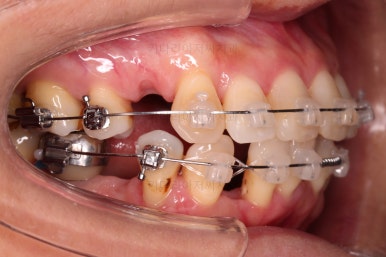

적절한 시점에 유치를 뽑아내고 남은 공간을 줄여나갑니다.

아래쪽 임플란트는 움직이지 않기 때문에 해당 치아를 기준으로 다른 치아를 모두 셋팅해야 하는 매우 난이도 높은 치료가 진행되었습니다.

발치 공간 앞뒤 치열을 당겨주어 공간을 줄여 나갑니다.

자연스레 입은 들어가게 될 것이고요.

임플란트는 크기가 작았으므로 교합을 위해서는 어쩔 수 없이 해당 부위에 틈이 남을 수 밖에 없었고요.

남은 틈은 임플란트 상부 보철을 재제작하면서 조절을 하기로 했습니다.